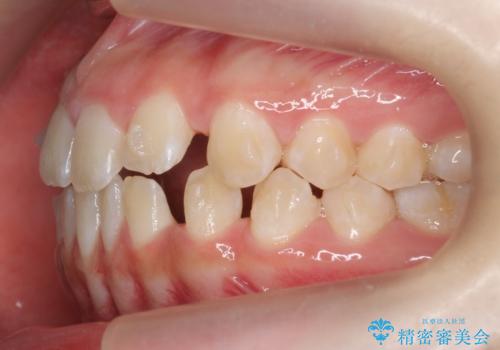

- 前歯の隙間を主訴に来院。

顎の大きさに比べて歯が小さく、隙間が目立っていました。

マウスピース矯正で隙間を閉じる処置を行いました。